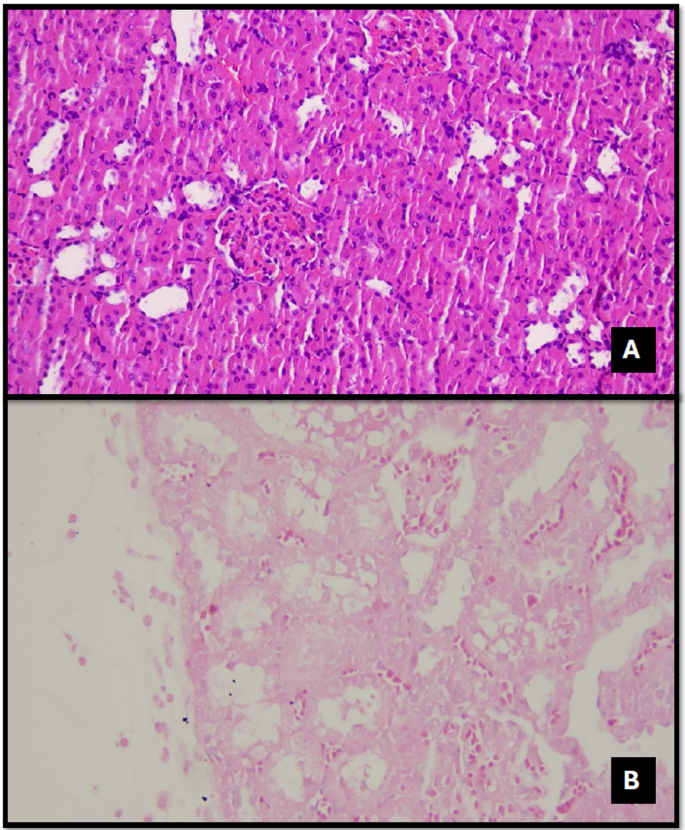

In the control group, renal structures were consistently within normal morphological limits across all histopathological examinations, with no evidence of inflammation, necrosis, or degeneration (Figs. 1, 2, 3, 4, 5, 6, 7, 8 and 9).

Tubular necrosis (Fig. 3) was not observed in the Control and DEX groups, but it was present in 50% of the TAC group and 12.5% of the TAC + DEX group. These findings were also found to be statistically significant (p = 0.048) (Table 3).

Tubular regeneration (Fig. 5) was identified in 87.5% of the DEX group and 100% of the TAC and TAC + DEX groups. A statistically significant difference was observed between the groups (p = 0.004) (Table 3).

Tubular dilation (Fig. 7) was observed in 16.7% of the Control (SF) group, 50% of the DEX group, 87.5% of the TAC group, and 100% of the TAC + DEX group. A statistically significant difference was detected among the groups (p = 0.003) (Table 3).